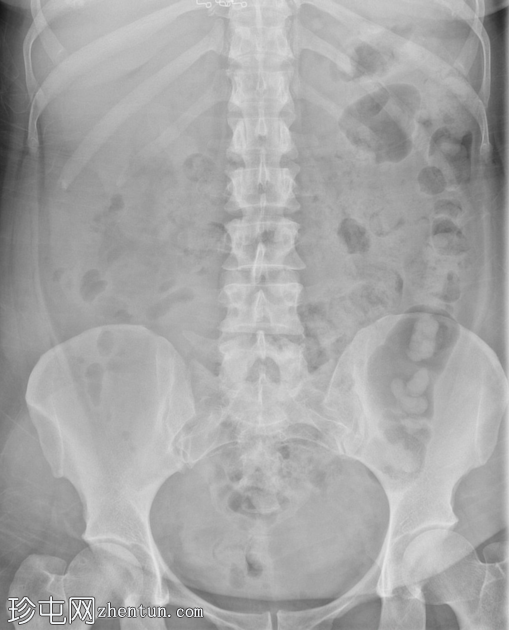

正位

经Foley导尿管向膀胱内注入约700毫升造影剂。

子宫内可见造影剂积聚,膀胱上表面与子宫之间存在异常瘘管连接。同时可见造影剂从输卵管溢入腹腔。

影像

学表现符合膀胱子宫瘘。